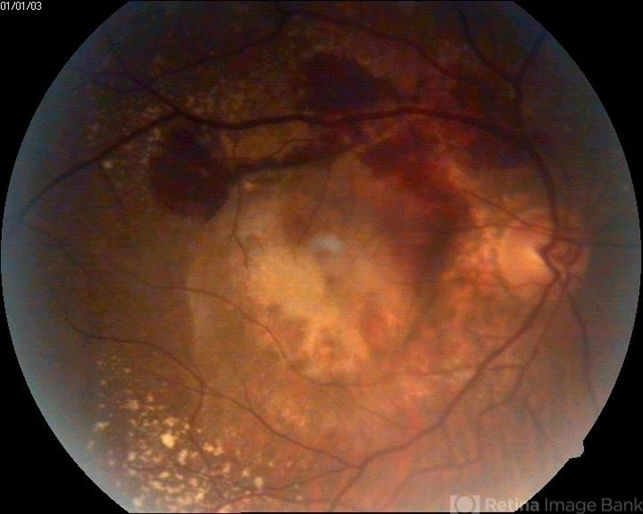

- A 65-year-old female patient presented with loss of vision and on examination found to have wet ARMD.